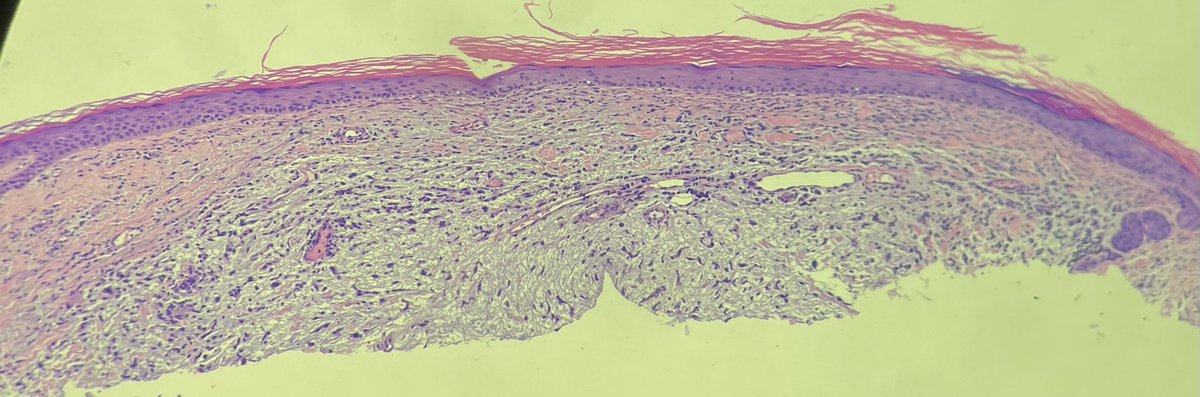

Calf. Elderly. Dx’s welcomed.

@tonitatirado @mccalmo @HENRYY_MD F13a and cd163 in order. @HENRYY_MD, are you the man now? Not perfect but??

Thanks all (@tonitatirado @mccalmo and @HENRYY_MD). Added some more IHC (cd168, F13a, pankeratin) that are probably low yield but odd lesion. Still think it’s focal mucinosis.

>70yo thigh. Eryrhematous nodule with hyperkeratotic scale. @mccalmo @HENRYY_MD Neg for CD34, sox10, cd30 (cd30 bc history said LyP, later found out it’s an autopopulate error). Focal cutaneous mucinosis? Cells are odd though.